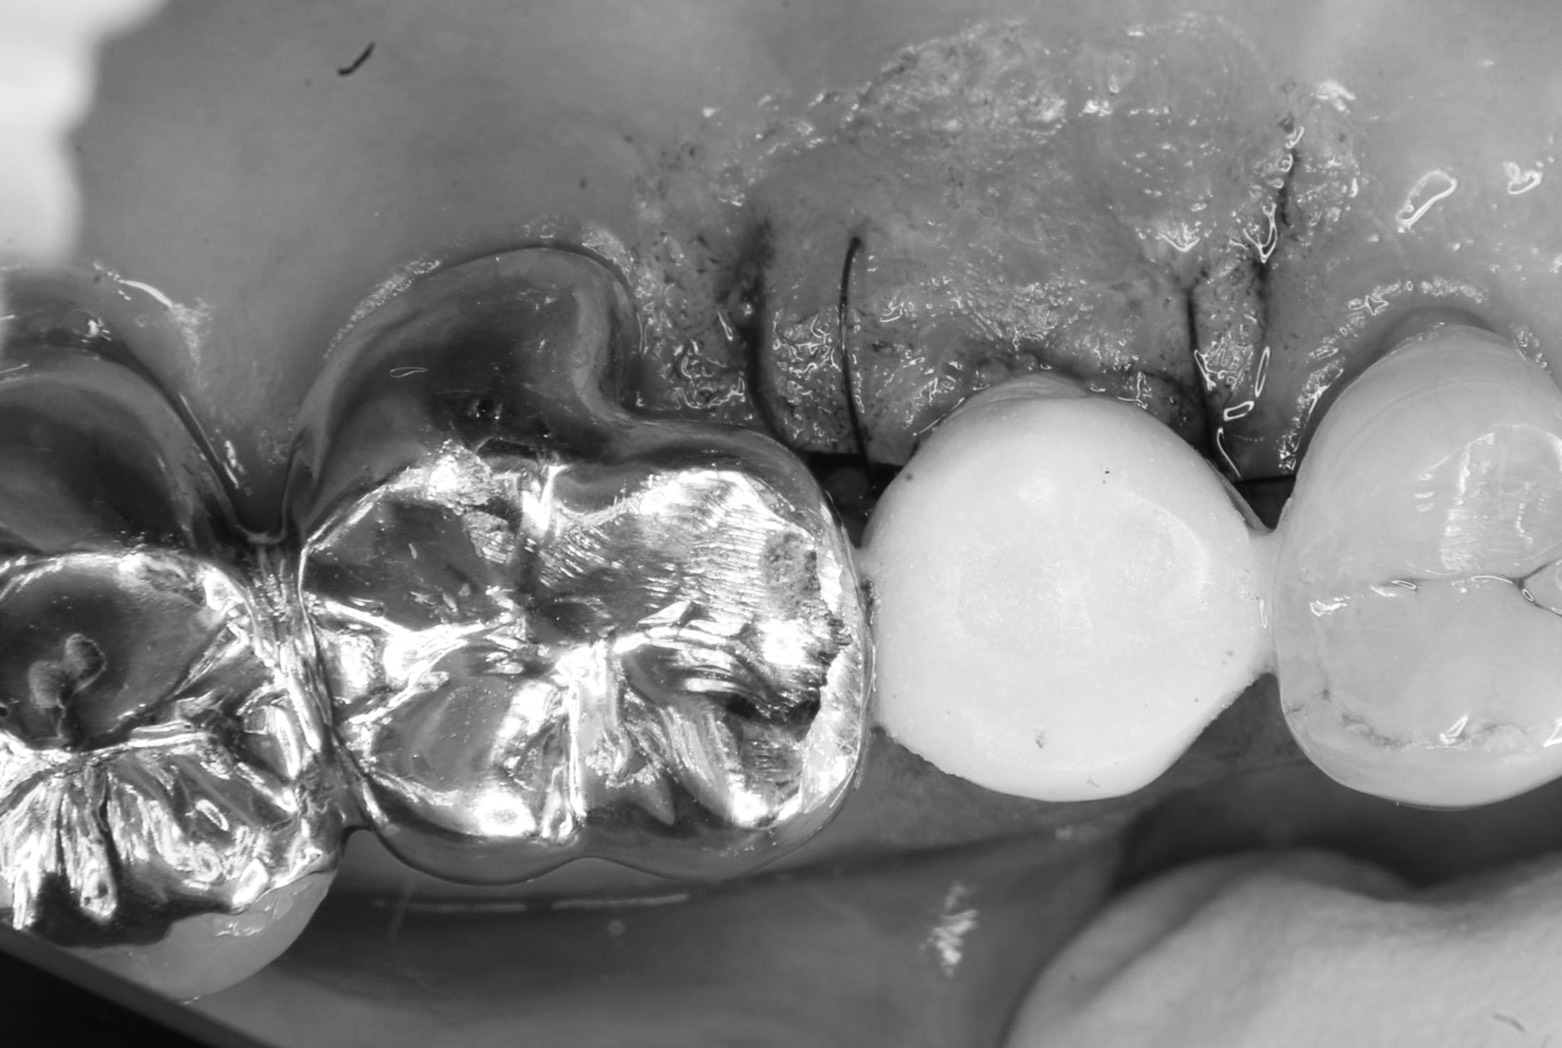

気持ち良い朝を迎えた3月最終日 分院では須田医師によるインプラントオペ 右上5番の抜歯即時埋入、同時に即時荷重(仮歯まで)がありました 抜歯から埋入

仮歯装着まで50分!

即時荷重用2種類の機器や器具を使いボーダ値をクリアして終了。

食事制限さえ守れれば問題はありません 患者さんにとっては、このスピード感は幸せな事ですね(^.^) 仮歯が無いと、発音、見た目も悪く、そんな患者さんサイドの気持ちを汲み込んだオペですが、難易度は上がります(´༎ຶོρ༎ຶོ`) オペの午後、早退しないように( T_T)\(^-^ ) 抜き打ちで終業時刻に電話入れますから! ご苦労様でした